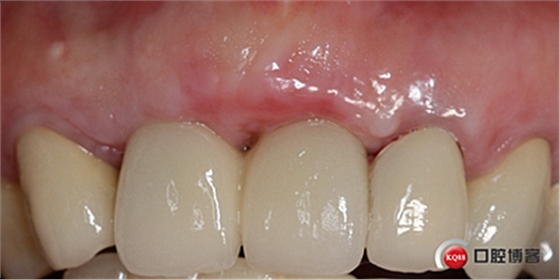

戴牙后半年復(fù)查。